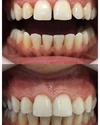

Zirkonyum uygulamalar

Porselen uygulamaları

Laminate veneer